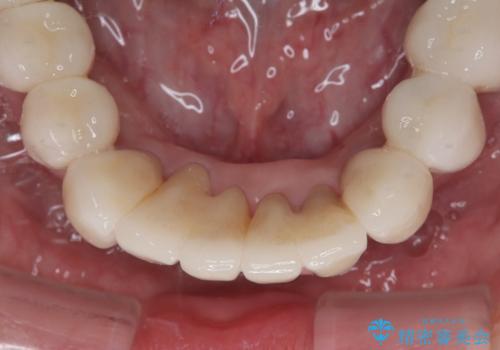

歯周病でグラグラの歯 矯正治療と歯周外科を併用した総合歯科治療

- 近医に通い続けるも、一向に不快感が改善しないとのことで来院された患者様です。

診察を行ったところ、重度歯周病の状態の上に上下の歯列が著しい叢生という状態でした。

歯周初期治療として抜歯や歯槽骨再生治療を行い、さらに歯周ポケット除去を行った後に矯正治療で歯列を整えて行くこととしました。

最終的には痛みや違和感のない状態にて治療を終えることができました。